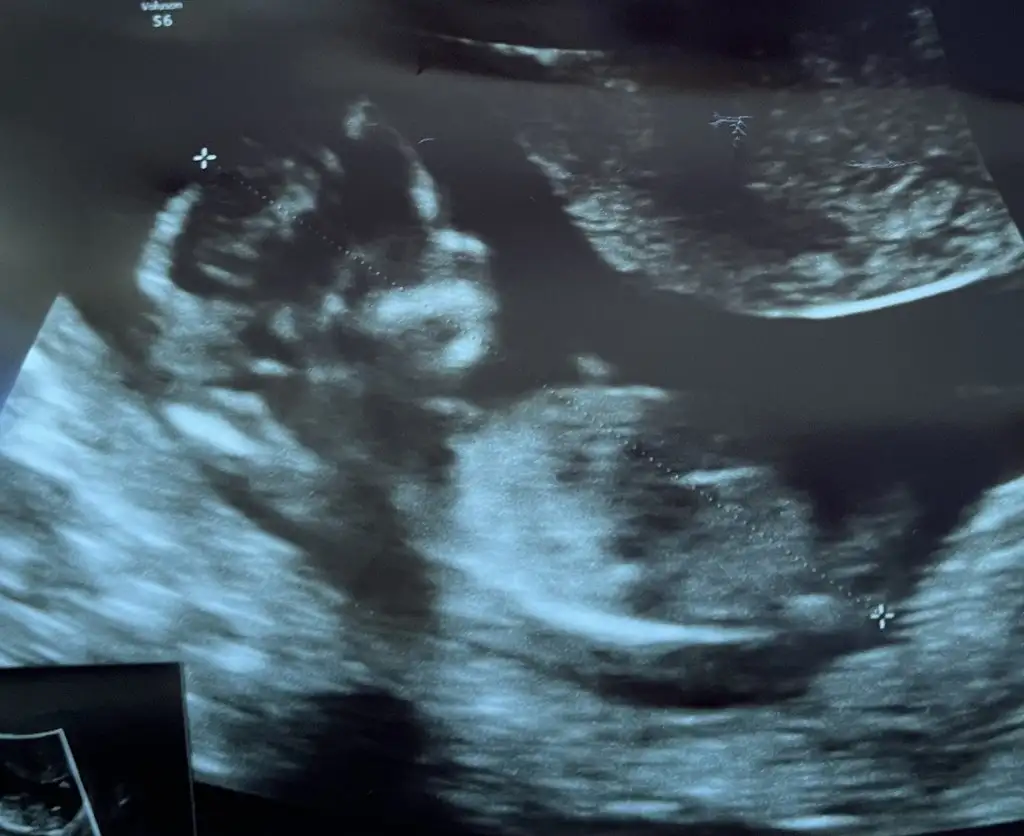

Kız görünüyor

Kız gibi sankiSabah da atmıştım ama görünmedi sanırım

12+6 yorumlarmısınız lütfennŞimdiden teşekkürler

Yan pozisyon daIkra meyra bana da bakarmısın 12+5

Kiz gibi sanki

Kiz gibi sanki en iyi 11 12 13 haftalar olmalı10 haftaligiz cinsiyet tahmini yapar mısınız lütfen Bn ikra hanimm